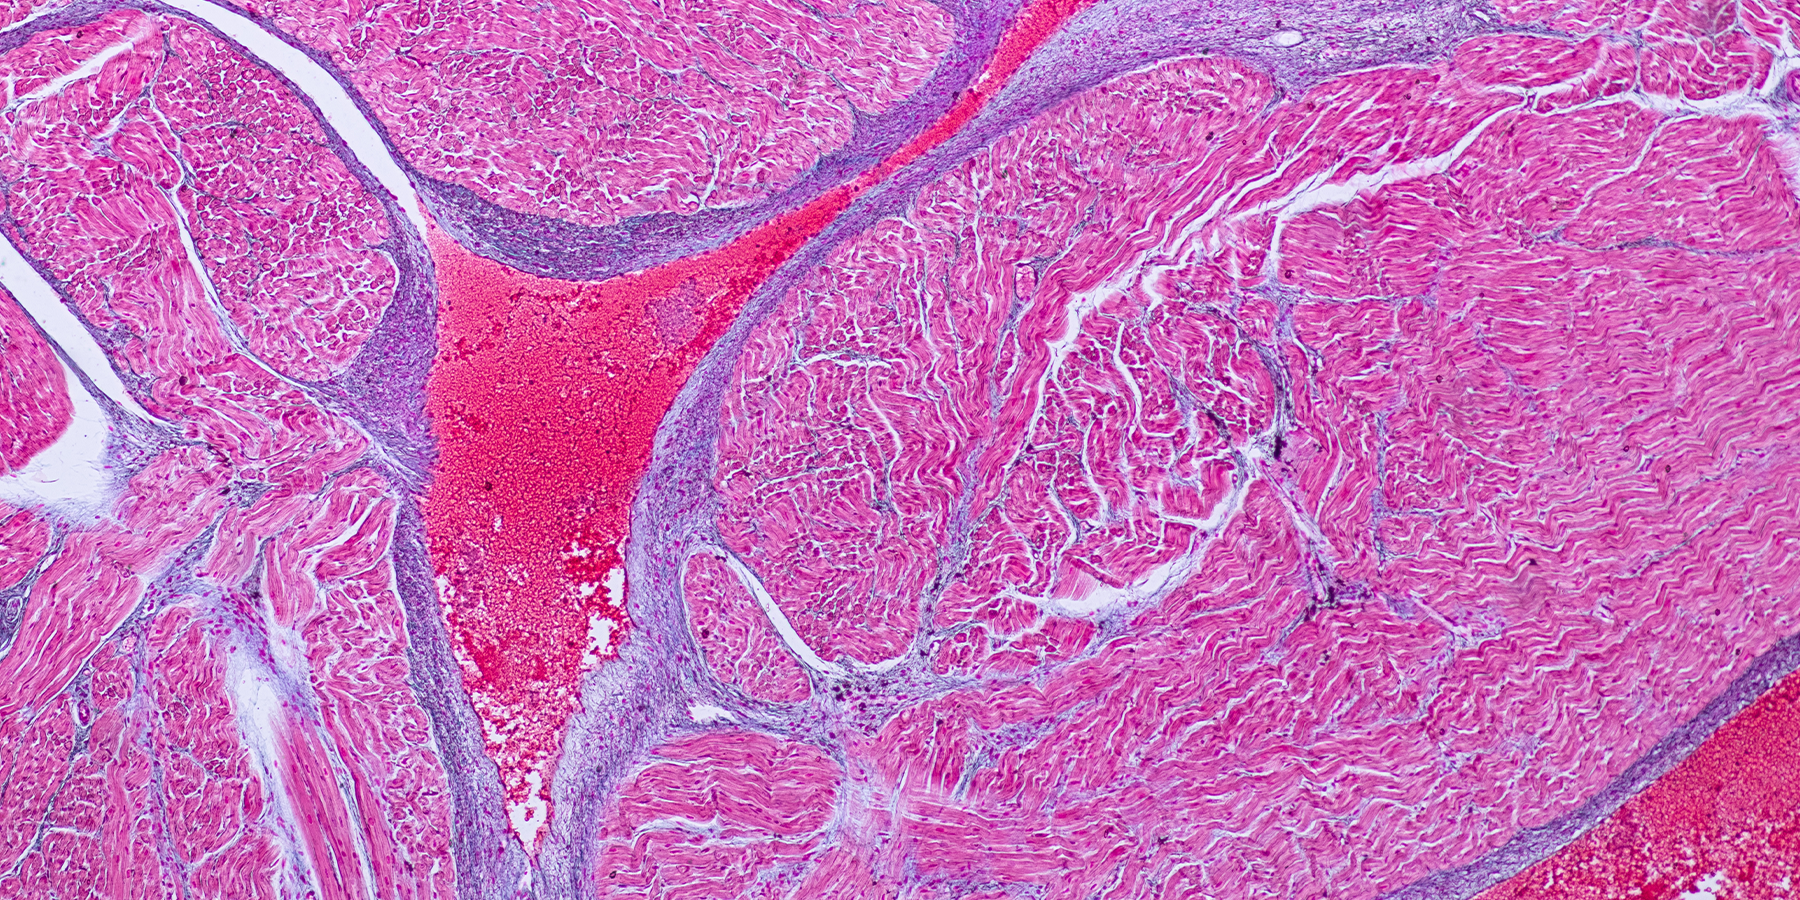

Now a team of scientists has created the first atlas of human heart cells, a collection of maps showing nearly half a million heart cells and identifying the role of each in the heart's symphony. The researchers examined six regions in 14 healthy donor hearts, creating a detailed database that provides a new basis of comparison for studying heart disease, the leading cause of death worldwide.

And healthy human hearts can be hard to find (most are used in transplants). Seidman's team relied on those unusual instances in which healthy hearts were rejected for transplantation and could be frozen for use in research. First, the researchers used a high-throughput sequencing method to define individual characteristics of every heart cell. They then mapped those cells in six regions of 14 human hearts, seven from men and seven from women. "For the first time, we have a zip code for each cell to know what population it belongs to," Seidman says.

Though the researchers studied a relatively small group of hearts ("fourteen people cannot replicate the world's population," Seidman says), the new atlas revealed some biological surprises. The team found previously unknown cell diversity in various parts of the heart. They also uncovered differences between the healthy hearts of males and females; females had a greater proportion of heart muscle cells, called cardiomyocytes, than males. That warrants more research, Seidman says, as those cells might hold clues to differences in heart disease between the sexes.

Still, "what we see is striking heterogeneity—in terms of the diverse cell types that we now know make up the tissue of the human heart, and in terms of the regional differences within the heart," says cardiologist Hugh Watkins of Oxford University in England, who was not part of the study team. "It's certainly a much more complicated organ than many might have imagined!"